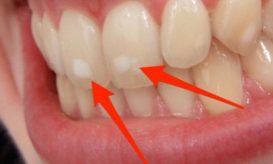

Η αισθητική οδοντιατρική μπορεί να αναβαθμίσει όχι μόνο την υγεία του στόματος αλλά και το πρόσωπο, με αποτέλεσμα να...